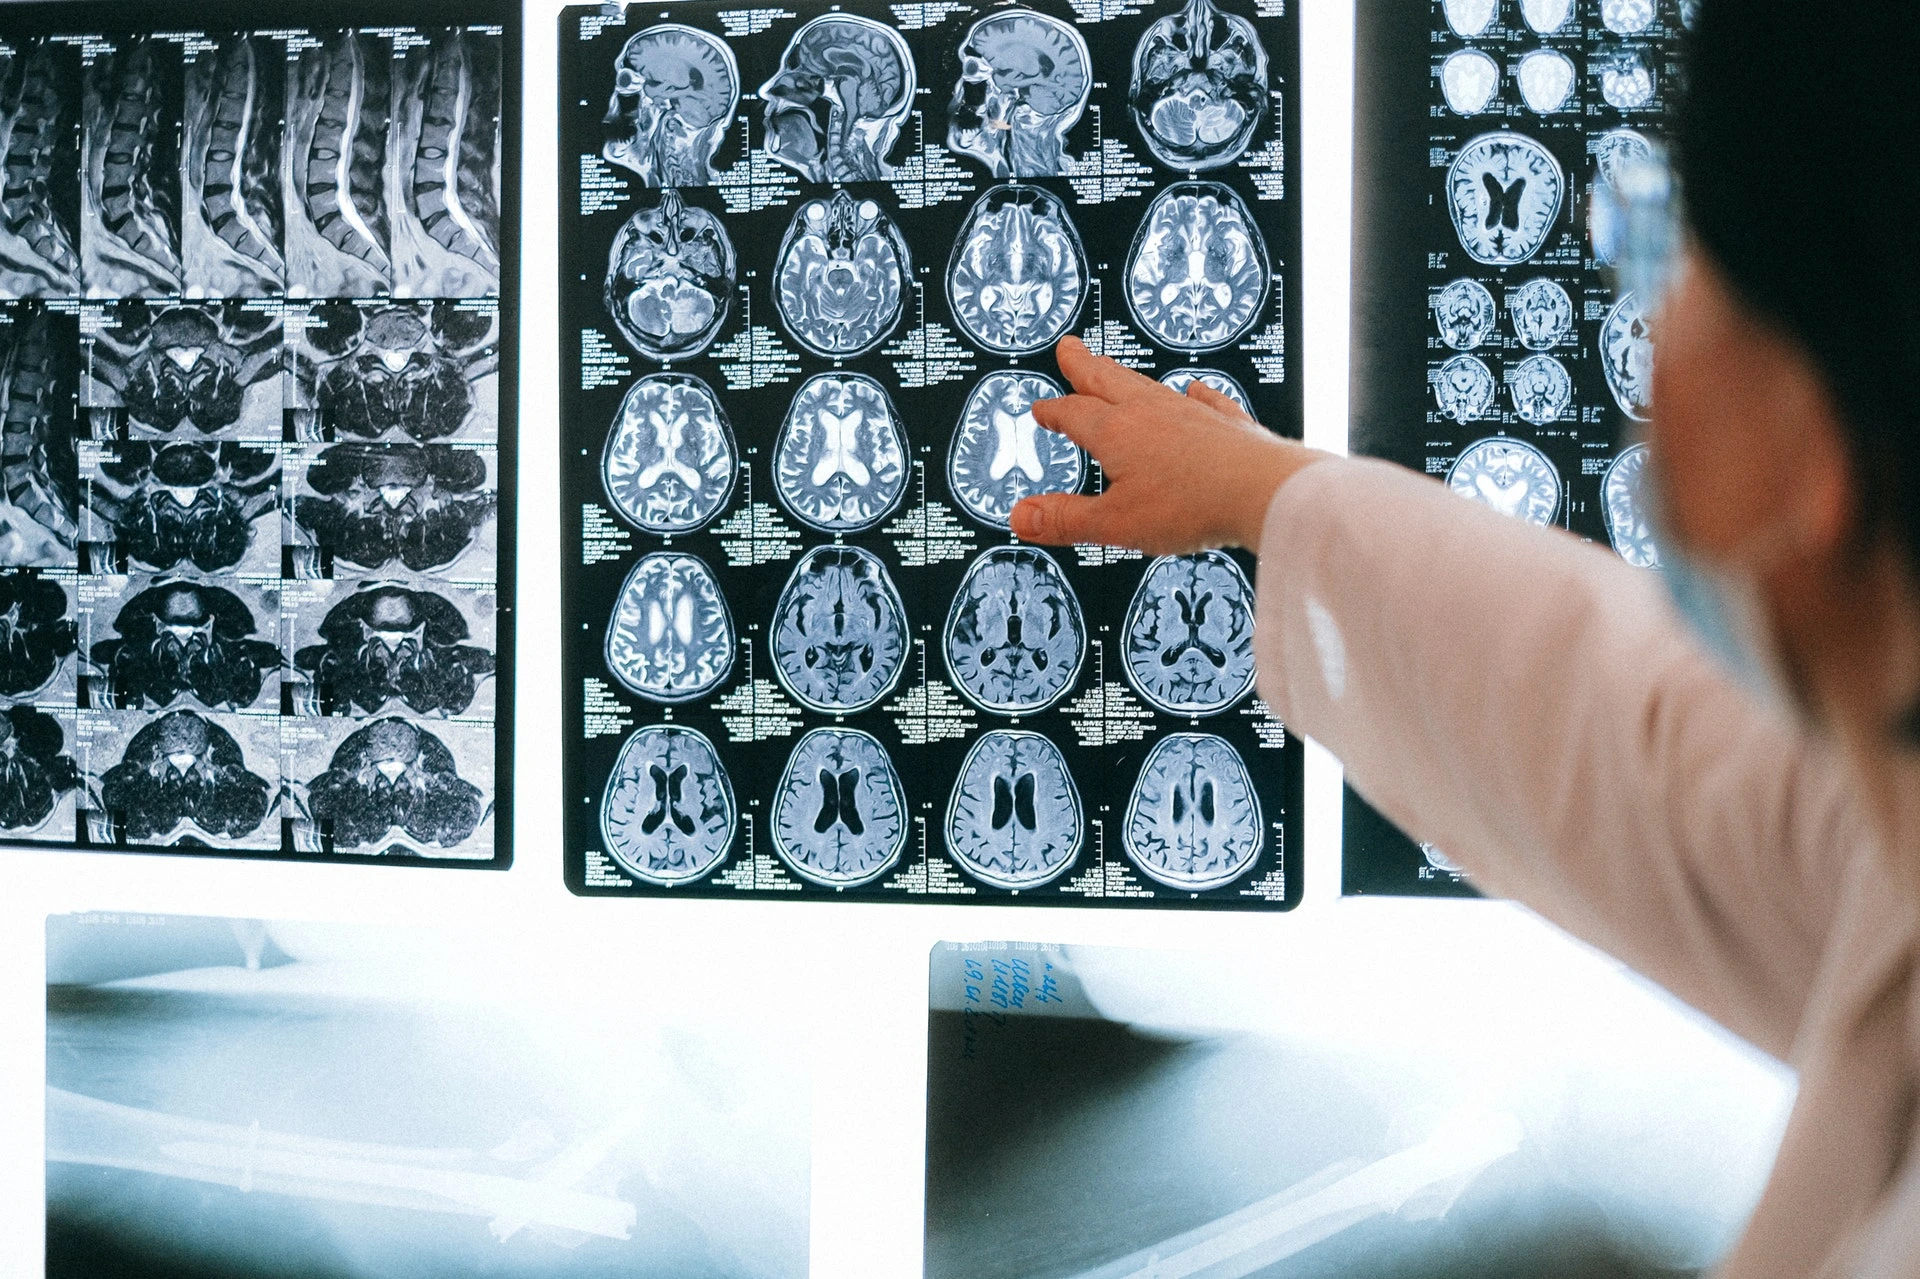

A causa de la pandemia de Covid-19, miles o incluso decenas de miles de personas podrían enfrentar problemas de por vida, también neurológicos. Por Sonia Villapol.

El coronavirus ataca principalmente a los pulmones, pero también a los riñones, corazón, hígado y vasos sanguíneos. Los datos clínicos hasta la fecha indican que el Covid-19 está asociado a trastornos neurológicos y neuropsiquiátricos.

Un estudio llevado a cabo en 500 pacientes hospitalizados con Covid-19 mostró que entre el 40 y el 60% de ellos experimentaba dolores de cabeza, confusión, delirio, o pérdida de memoria, lo que sugiere que el virus también puede atacar el cerebro. En casos muy esporádicos se ha descrito psicosis no asociada con la gravedad de la enfermedad.

No todos estos síntomas tienen por qué ser causados por la invasión del virus a las células cerebrales. Pueden ser el resultado de una inflamación generalizada en todo el cuerpo. Por ejemplo, la inflamación de los pulmones puede liberar moléculas que hacen que la sangre se vuelva pegajosa y obstruyan los vasos sanguíneos, provocando accidentes cerebrovasculares.

Además, muchos síntomas neurológicos pueden ser el resultado de la tormenta de citoquinas y la sobreestimulación del sistema inmunológico periférico que afecta al cerebro. Necesitamos aclarar las vías por las que el virus afecta al cerebro a través de la inflamación o la infección, ya que los tratamientos podrían ser diferentes.

Sabemos que el SARS-CoV-2 utiliza receptores de la enzima convertidora de angiotensina 2 (ACE2) y sus co-receptores para invadir las células. El virus también puede alcanzar la vasculatura cerebral a través de la circulación sanguínea, al unirse al receptor ACE2 expresado en las células endoteliales de los capilares cerebrales, cruzar la barrera hematoencefálica e invadir y lesionar el parénquima cerebral.

Aun así, la infección cerebral es rara, probablemente porque las neuronas expresan pocos receptores para ACE2. A pesar de esto, algunas personas pueden ser más susceptibles debido a antecedentes genéticos, una carga viral alta u otras razones. Es necesario estudiar cuáles son las predisposiciones por las que los problemas neurológicos suceden en los pacientes de Covid-19.

Estudios recientes han confirmado que el accidente cerebrovascular isquémico, la trombosis venosa cerebral y la hemorragia cerebral son comunes en pacientes de edad avanzada con Covid-19, pero representarían sólo del 1 al 5% de los pacientes hospitalizados. Un estudio del Hospital General Universitario de Albacete determinó que el 1,4% de los pacientes con Covid-19 presentaron problemas cerebrovasculares con alta morbilidad y mortalidad.

El daño del SARS-CoV-2 en el cerebro se está estudiando en modelos animales, en organoides –cerebros en miniatura cultivados in vitro–, o en los cerebros de autopsias de pacientes con Covid-19. En estos últimos se observó, por medio de microscopía electrónica o técnicas de inmunohistoquímica, cómo el virus invadía las neuronas.